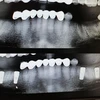

Zirkonyum uygulamalar

Porselen uygulamaları

Laminate veneer